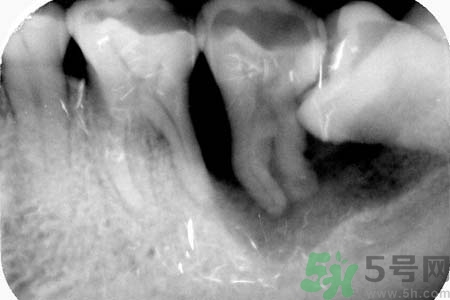

針對(duì)長(zhǎng)歪了的智齒,專家建議及早的拔智齒處理,至于拔智齒多少錢,一般來(lái)說(shuō)拔智齒多少錢在150—300元左右,具體根據(jù)智齒的拔除難易程度而定,如果智齒阻生較為嚴(yán)重的話,在拔智齒前還需要拍x光片以了解智齒及鄰牙的具體結(jié)構(gòu),這種情況下,拔智齒多少錢相對(duì)要貴一些。

三級(jí)醫(yī)院阻生智齒拔除術(shù)收費(fèi)標(biāo)準(zhǔn)是85元,加上切開(kāi)縫合放藥等也不到200元。拍牙片不計(jì)入(牙片有10元的也有80元的)這顆牙較難拔,術(shù)后反應(yīng)也大,最好去正規(guī)醫(yī)院拔。